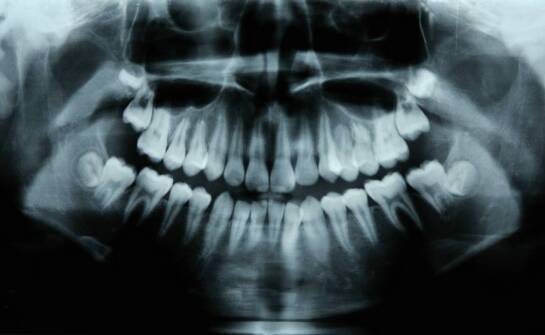

Tomografia komputerowa zębów (CBCT) to szybkie, bezbolesne badanie 3D, które lekarz wykorzystuje do precyzyjnej diagnostyki i planowania leczenia. Do badania nie trzeba się specjalnie przygotowywać: wystarczy zdjąć metalowe elementy. CBCT wykrywa próchnicę, zmiany w kości i zatokach, torbiele, guzy,